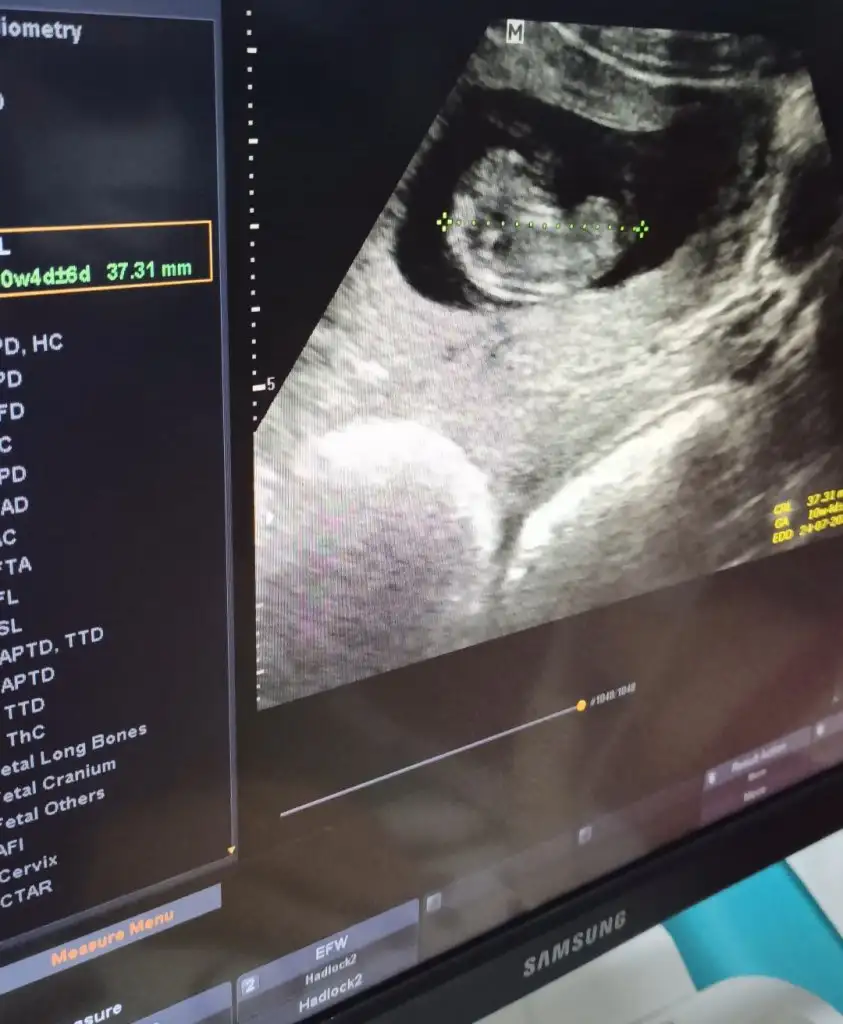

Merhaba Ikra meyra 10+4 CRL de 11+2 çıktı. Cinsiyet tahmininde bulunabilir misiniz?

Teşekkür ederim